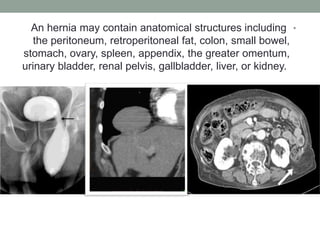

An hernia may contain anatomical structures including

the peritoneum, retroperitoneal fat, colon, small bowel,

stomach, ovary, spleen, appendix, the greater omentum,

urinary bladder, renal pelvis, gallbladder, liver, or kidney.